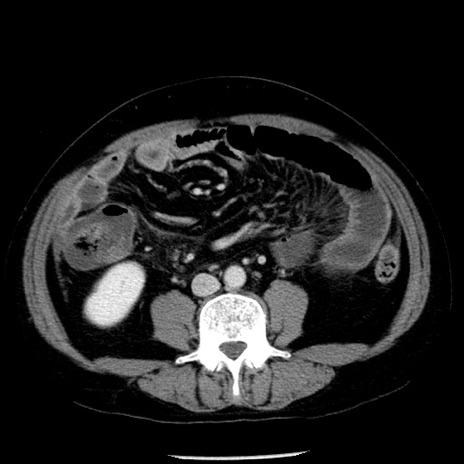

症例29(横断像)

【症例】40歳代男性

【現病歴】2日前から胃痛あり。徐々に周期的な激痛に変化した。本日になっても激痛があるため受診。

【身体所見】意識清明、BT 38-39℃台あり、腹部:膨満、やや硬、右下腹部に圧痛あり。

【データ】WBC 8500、CRP 23.26